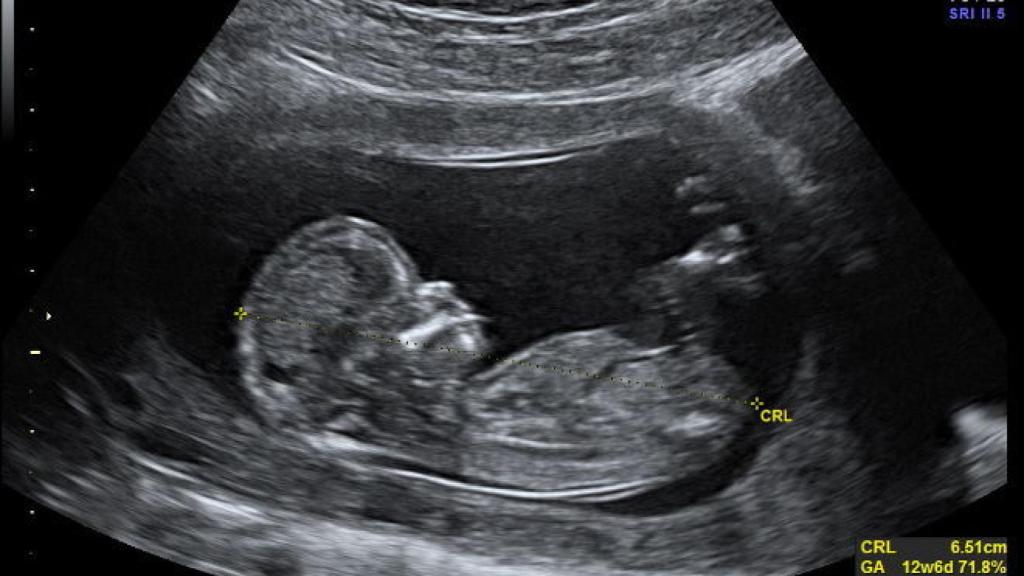

Hay muchas maneras de detectar problemas durante el embarazo, pero todos conllevan sus propios problemas; ya sea porque no aportan una imagen clara de la situación del feto, o bien por el alto porcentaje de falsos positivos (sobre el 3.6% en análisis de sangre), es necesario estandarizar otro método mas preciso y fiable. Y ese puede suponer analizar el ADN fetal.

Entre el 10% y el 20% del ADN que circula en el flujo sanguíneo de una embarazada proviene del mismo feto, y por tanto puede servir para analizar y prever enfermedades genéticas antes del parto. Sin embargo, normalmente este tipo de análisis se reserva a madres de alto riesgo, ya sea por edad (mas allá de los 35 años) o porque su familia tiene historial de enfermedades genéticas.

Ahora un estudio publicado en el New England Journal of Medicine asegura que este tipo de análisis también pueden usarse en madres de bajo riesgo para comprobar si el feto desarrollará enfermedades como el síndrome de Down, con un porcentaje de falsos positivos muy bajo, del 0.3%. Por lo tanto, este método podría sustituir otros mas invasivos o ineficientes como los ultrasonidos o las biopsias coriales.